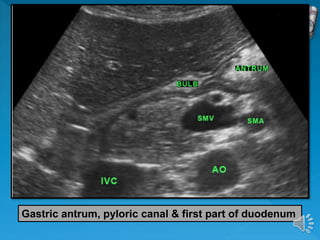

Gastric antrum, pyloric canal & first part of duodenum

 The duodenum is identified by its “C-shaped”

course around the pancreatic head.

 The first part of the duodenum is seen just

distal to the pylorus.

 The third part of the duodenum lies between

the aorta and the superior mesenteric vessels

Gastric antrum, pyloriccanal & first part of duodenum

 The duodenumis identified by its “C-shaped” course around the pancreatic head.  The first part of the duodenum is seen just distal to the pylorus.  The third part of the duodenum lies between the aorta and the superior mesenteric vessels